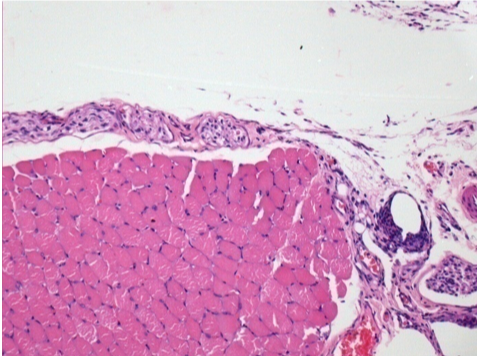

Control

Comentario: Nada que declarar después de la inyección de solución salina.

L: Pretibial-Sin tratamiento

R: Pretibial-Después de 0,1 ml de NaCl 0,9% IM